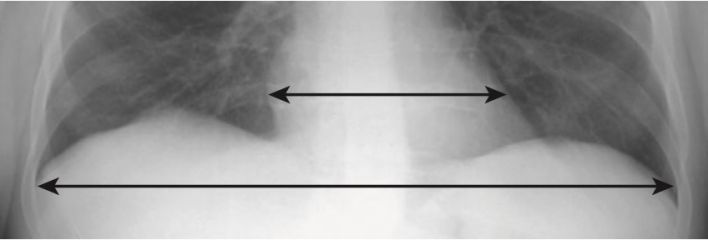

- Có thể ước tính kích thước của bóng tim trên phim chụp X quang ngực thẳng bằng tỷ lệ tim – lồng ngực, so sánh đường kính ngang rộng nhất của tim với đường kính trong rộng nhất của khung xương sườn (thường ngang mức cơ hoành) (Hình 1).

- Ở hầu hết người lớn bình thường khi hít vào tối đa (thấy được khoảng 9 xương sườn sau), tỷ lệ tim lồng ngực <50%.